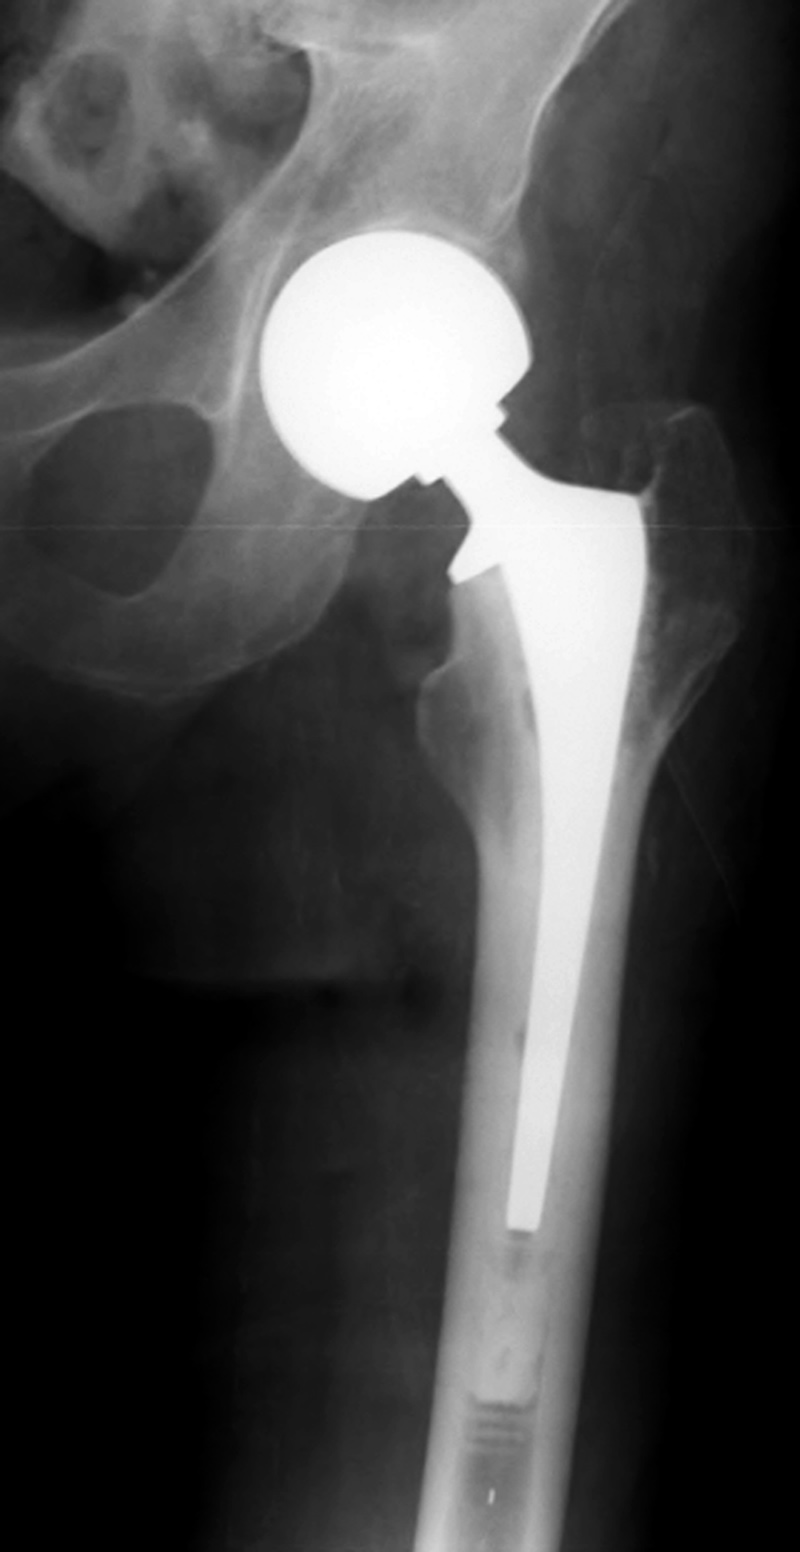

Revision total hip prosthesis |

The revision prosthesis was placed because of an earlier periprosthetic fracture. There are two cable wires proximally and two cerclage wires distally. From Taljanovic, 2005 |